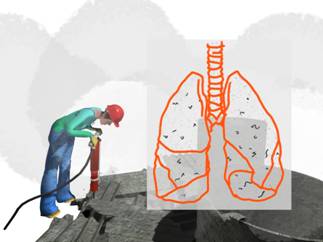

- El amianto es una fibra natural que, por sus características tecnológicas excepcionales, como su difícil inflamabilidad, buena resistencia térmica y mecánica, su buena resistencia a los ácidos y álcalis, resistencia al paso de la electricidad y a los microorganismos, se ha utilizado en múltiples aplicaciones de ámbitos tan variados como en construcción, industria y productos de gran consumo.

Voz en off Chica- La exploración clínica específica debe incluir la inspección y la auscultación.

Voz en off Chica- El estudio radiológico del tórax. En función de los resultados se podrán hacer otras pruebas como una tomografía computada o una tomografía computada de alta resolución.

Voz en off Chica- Estudio funcional respiratorio: espirometría forzada. También se podrán solicitar otras pruebas como un test de difusión, una exploración de los volúmenes pulmonares o una prueba broncodilatadora.

Voz en off Chica- Considerando el incremento del riesgo de sufrir cáncer de pulmón derivado de la exposición conjunta al amianto y al tabaco, es importante incluir este punto en los exámenes de salud.